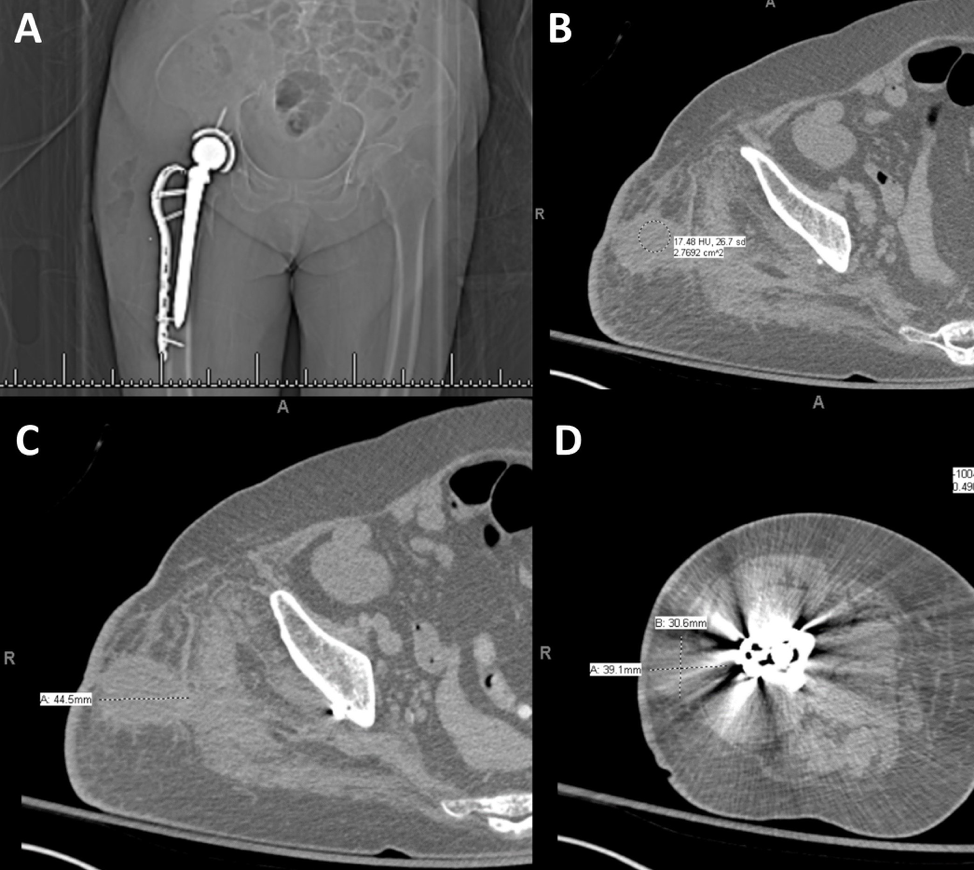

One month after discharge from her total hip arthroplasty and revision, she was seen by orthopedics outpatient and was noted to have increasing right hip pain, in addition to erythema and serosanguinous drainage at the incision site. She was started on cephalexin for a presumed infection. Two days later, her hip pain significantly increased and she sought care at an emergency department for re-evaluation. A CT of the lower extremity without contrast was performed and showed a large, gas-containing collection in the lateral soft tissues of the right pelvis/femur, extending from the iliac crest through the proximal femur, involving the right gluteal musculature— concerning for infection. The patient was taken to the operating room the next day where necrotic and purulent material was found and surgically debrided. Cultures obtained were consistently positive for Clostridium difficile (C. diff), which was treated with piperacillin/tazobactam and metronidazole for six weeks. Cultures were found to be susceptible to amoxicillin/clavulanate and thus following the patient’s six week course of piperacillin/tazobactam and metronidazole, her regimen was changed to amoxicillin/clavulanate for indefinite suppression.